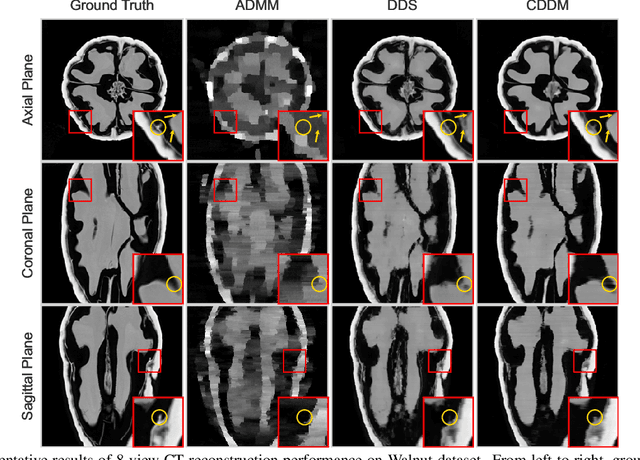

Abstract:Sparse-view Computed Tomography (CT) image reconstruction is a promising approach to reduce radiation exposure, but it inevitably leads to image degradation. Although diffusion model-based approaches are computationally expensive and suffer from the training-sampling discrepancy, they provide a potential solution to the problem. This study introduces a novel Cascaded Diffusion with Discrepancy Mitigation (CDDM) framework, including the low-quality image generation in latent space and the high-quality image generation in pixel space which contains data consistency and discrepancy mitigation in a one-step reconstruction process. The cascaded framework minimizes computational costs by moving some inference steps from pixel space to latent space. The discrepancy mitigation technique addresses the training-sampling gap induced by data consistency, ensuring the data distribution is close to the original manifold. A specialized Alternating Direction Method of Multipliers (ADMM) is employed to process image gradients in separate directions, offering a more targeted approach to regularization. Experimental results across two datasets demonstrate CDDM's superior performance in high-quality image generation with clearer boundaries compared to existing methods, highlighting the framework's computational efficiency.